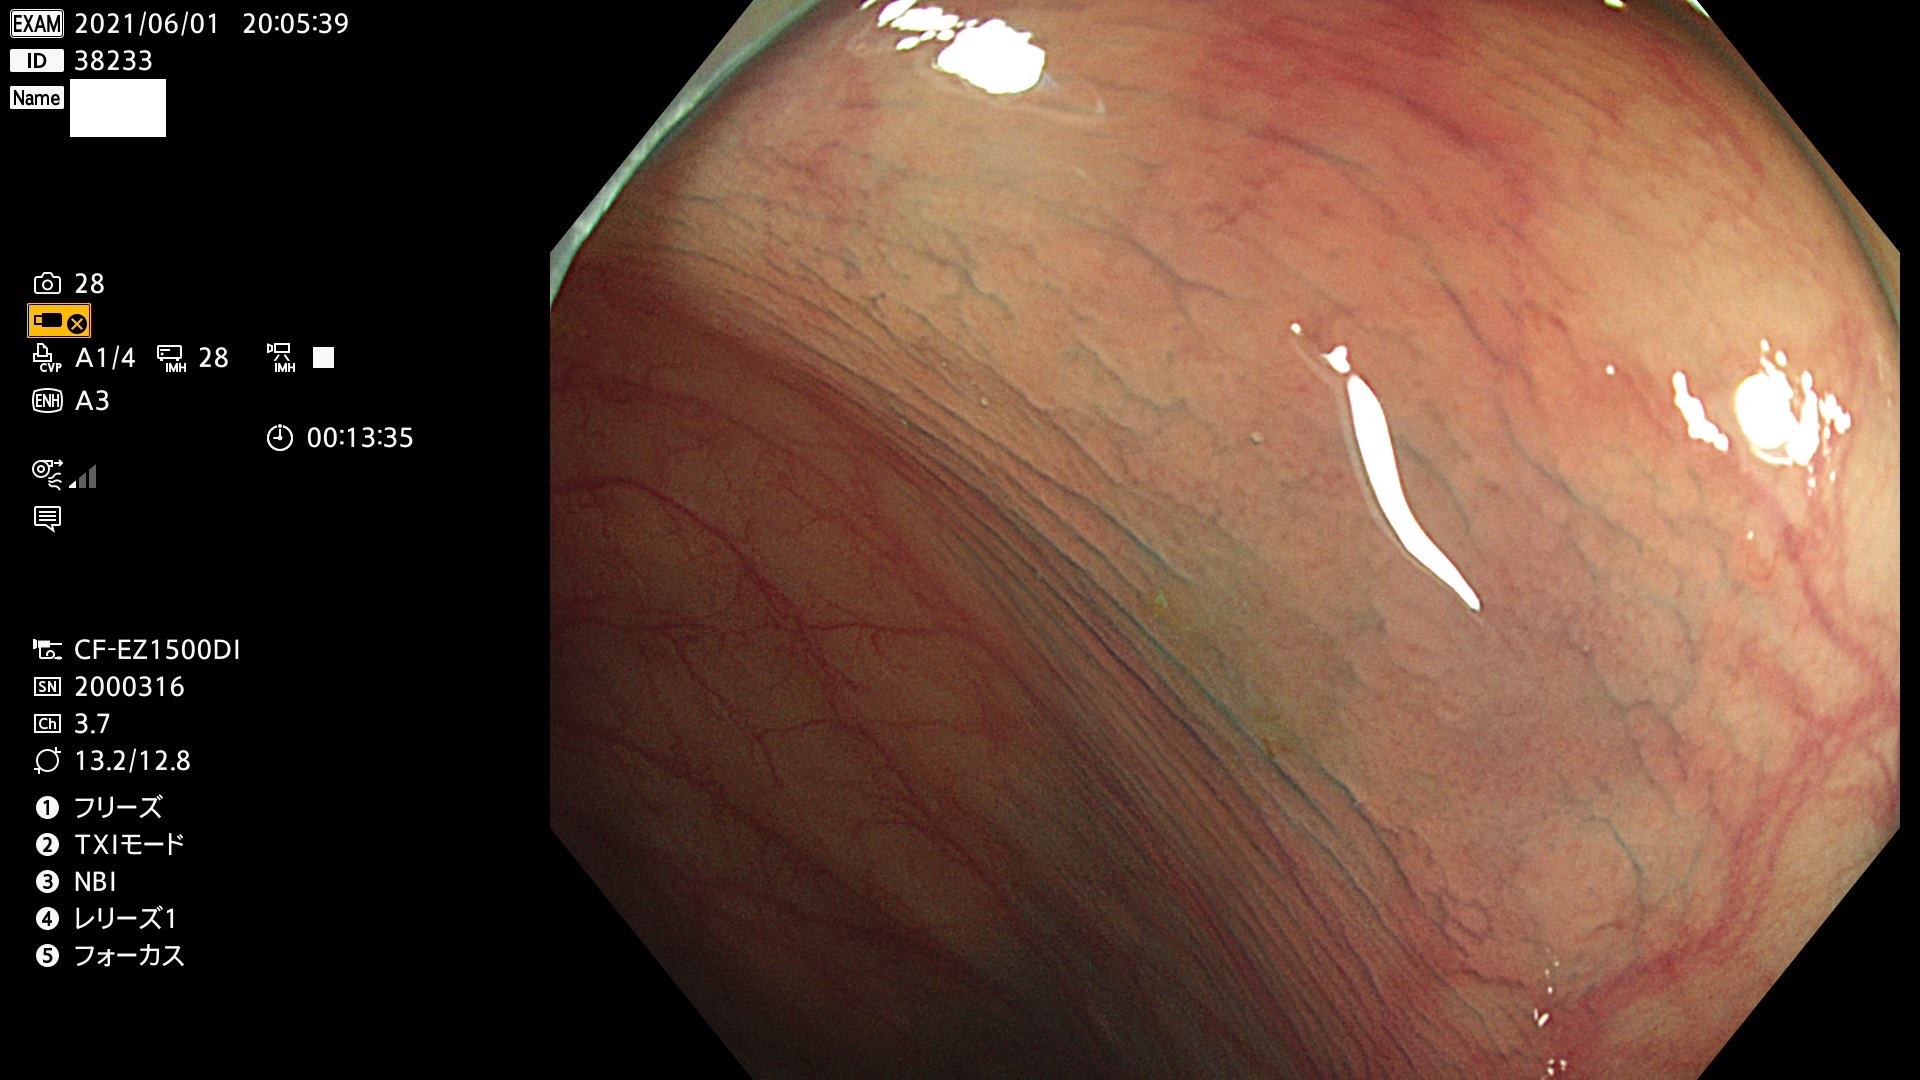

38200 38201 38202 38203 38204 38208 38209 38210 38211 38212 38213 38214 38215 38219 38220(SSAPのみ) 38221 38225 38226 38227 38228 38229 38230 38231 38232(SSAPのみ) 38233 38234 38235 38237 38238 38239 38240 38241 38242 38244 38245 38246 38247 38248 38249 38250 38251 38252 38253 38254 38256 38257 38258 38259 38260(SSAPのみ) 38262 38265 38267 38268(SSAPのみ) 38269 38270 38272 38273 38274 38276 38278 38280 38281 38282 38283 38284 38287 38288 38289 38290 38291 38292 38295 38296 38297 38298 38299(SSAPのみ)

発見困難で危険性の高い平坦型病変(上記100名より抽出)